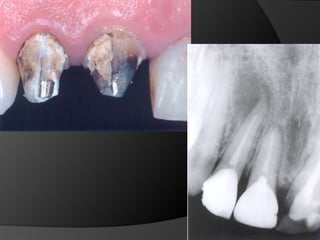

La literatura ha demostrado que los dientes restaurados con coronas pueden sufrir daños pulpares, pues aproximadamente 1 a 2 millones de túbulos dentinales (30.000 a 40.000 túbulos por mm2 de dentina) son expuestos durante una preparación dental

Técnicas anestésicasCalor generadoCalidad de las fresas y de la turbinaCantidad de dentina remanenteProcedimientos de impresión y materialesGrado de Filtración Marginal

fundamentos de periodoncia en prótesis fijaCuando, por la evolución de lesiones de caries, fracturas, o necesidad de ganancia de retención mecánica en pilares muy cortos, el espacio biológico es violado, existe la necesidad de restablecer sus dimensiones, como una forma de recuperar la salud del periodonto y de facilitar los procedimientos protésicos